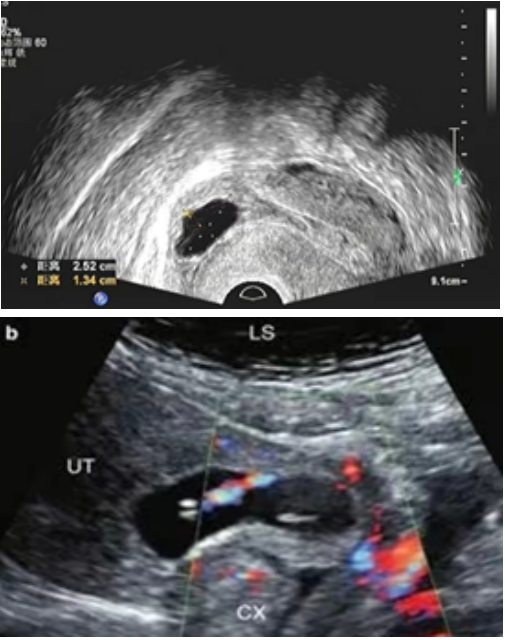

🔹III型

妊娠囊完全着床于子宫瘢痕处肌层并向膀胱方向外凸;

• 妊娠囊与膀胱之间子宫肌层变薄,甚至缺失,厚度≤3mm;

• CDFI:瘢痕处见滋养层血流信号(低阻血流)。

🔹III型中特殊的超声表现:包块型

• CDFI:包块周边见较丰富的血流信号,可为低阻血流,少数也可见少许血流信号、或无血流信号。